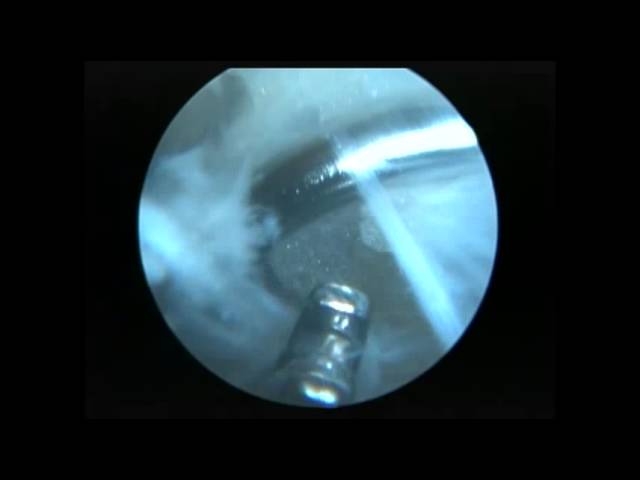

QUIRÚRGICOS

Prótesis de cadera, rodilla, hombro. Artroscopia; hombro, cadera, rodilla, tobillo, fracturas. Operamos en Nova Clínica Santa Cecilia, Axxis Hospital y Clínica Pasteur